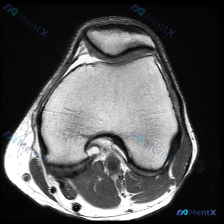

今天遇到一个有意思的读片问题:只给了一张膝关节轴位MRI,问这里有没有软骨异常,整理一下分析思路分享给大家。 基本病例/影像信息 提供的是膝关节单张轴位MRI扫描图像,可识别的解剖结构包括:前方的髌骨、中部的股骨内外侧髁与髁间窝、髌股关节间隙,以及周围部分软组织。 客观影像所见 1. 软骨结构:髌骨...

看到一份针对单张膝关节MRI的软骨异常评估咨询,整理了完整的分析思路分享给大家。 病例/影像基础信息 问题核心:用户提供单张膝关节轴位T1加权MRI图像,询问图像中是否存在软骨异常。 影像所见(基于提供图像): 1. 扫描层面为膝关节轴位,涵盖股骨远端滑车区与髌骨 2. 股骨髁、髌骨骨髓信号正常(T...

刚遇到一份有意思的膝关节影像病例,整理出来和大家分享一下思路。 病例基本信息 这是一份膝关节MRI T1序列轴位单张图像,核心疑问是评估是否存在「软骨异常」。 影像读片结果 1. 扫描层面是膝关节上部,主要显示髌股关节(髌骨+股骨滑车)和股骨髁 2. 髌骨软骨下骨、股骨髁骨皮质轮廓清晰,骨松质信号均...

病例读片:膝关节软骨异常的影像陷阱 先给大家看一下这份病例的基本影像资料:这是一张膝关节MRI-T1加权序列的轴位图像,扫描层面位于股骨远端髁间窝与髌股关节层面。 影像基本信息整理 1. 骨骼结构:股骨远端骨皮质、骨髓信号正常,髌骨形态完整,骨皮质连续,骨髓信号无异常; 2. 关节软骨:髌骨后方关节...